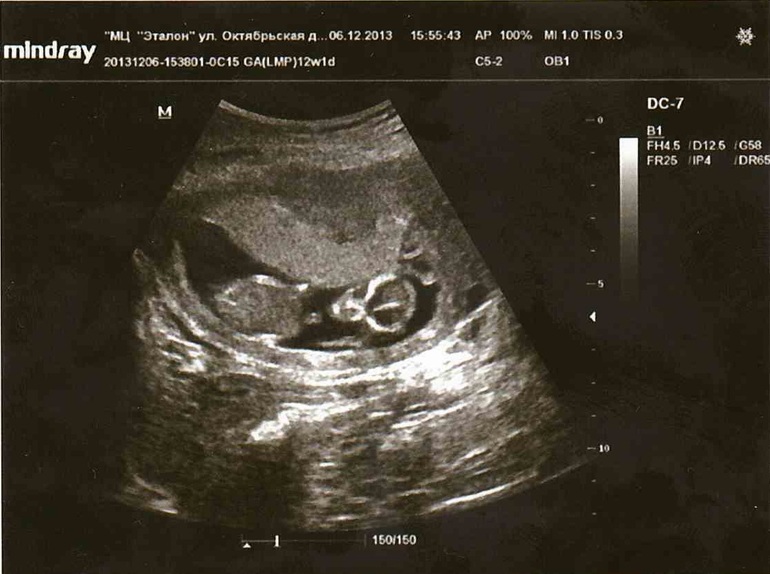

Помогите определить мальчик или девочка!!

Очень хочется знать кто у меня. По УЗИ 12,1 недель. Сердцебиение 162. КТР 67.

Что думаете?

При таком положении не определить, надо смотреть в профиль угол наклона пипирки.